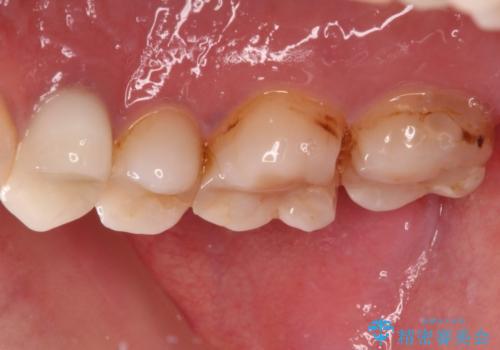

- 奥歯の詰め物や周辺の歯が欠けてしまったとのことで来院された患者様です。

上顎は、元々の詰め物が小さく、欠けた範囲も大きくなかったため、セラミックインレーにて修復治療を行うこととしました。

一方下顎は、元々のむし歯の範囲が広かったため、長期的な予後を踏まえ、セラミッククラウンにて補綴治療を行うこととしました。

特に痛みはありませんでしたが、未然にしっかりとした処置を行うことで、今後むし歯の進行により神経組織が壊死するリスクを低減することが可能となります。